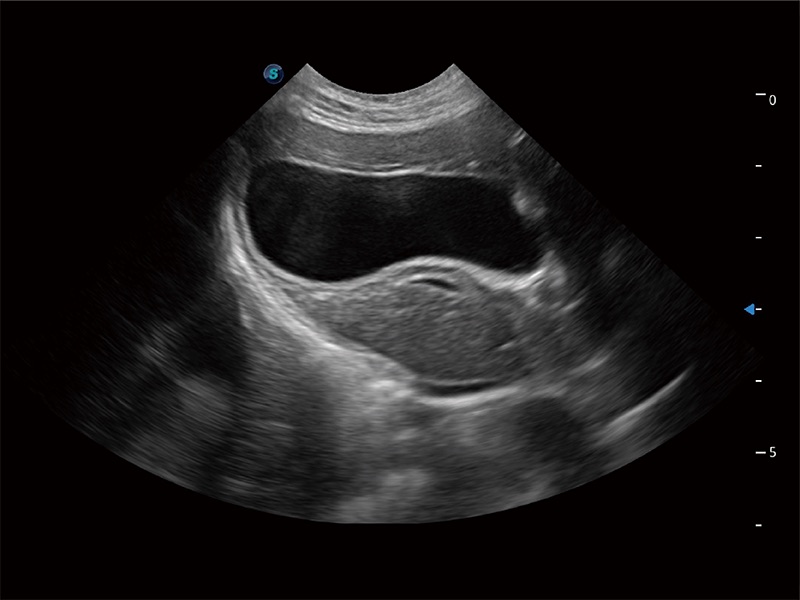

一键自动识别膀胱壁及自动测量膀胱容积,不受膀胱形状和大小的限制,帮助医生快速精准获得测量的数据。

ProPet 80 专为动物医生设计,对不同的动物体型和生理结构作出了针对性的优化。通过动物影像专用软件,可满足个性化的应用需求,帮助动物医生获得更精确的诊断数据。

为精细结构及组织边缘提供高清晰度的图像和更大的成像视野。帮助减轻医生的用眼疲劳,快速精准获得测量的数据。